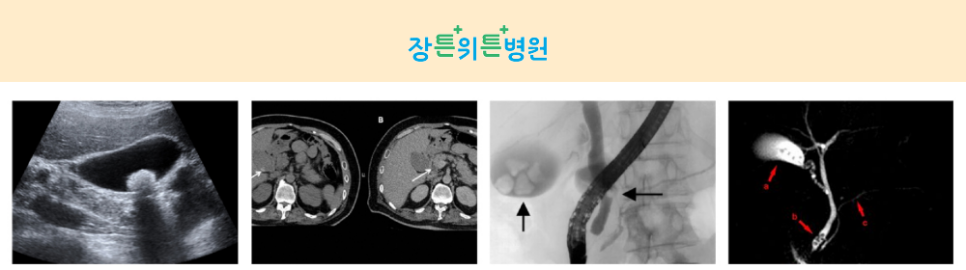

- 복부초음파검사 담석증이 의심되는 경우 복부총음파검사를 실시할 때 담낭 담석은 90%이상 발견할 수 있으나 간이나 담관내 담석은 정확도가 떨어질 수 있습니다.무증상담석 또는 급성 통증만의 담낭담석의 경우 혈액검사에서는 특별한 이상소견이 없는 경우 복부초음파검사를 통해 담낭결석을 확인합니다.

- – 복부전산화단층촬영(CT)전산화단층촬영은 X선을 이용하여 몸의 단면을 영상화하는 비침습적 검사방법입니다.여러 장기를 동시에 볼 수 있다는 장점이 있어 이 검사를 통해 담석을 발견하고 이에 따른 합병증인 담낭, 담관 감염과 천공을 확인할 수 있습니다.

- – 담도조영술(ERCP) 특수 내시경을 이용하여 담관과 췌관을 관찰하는 침습적 검사방법으로 십이지장에 내시경을 삽입하고 담관에 조영제를 투입하여 담관 내 담석을 관찰하면서 치료도 동시에 시행합니다.

- – 자기공명담관 췌관영상(MRCP) 흔히 MRI로 알려진 자기공명영상은 초전도 자석과 고주파를 발생시켜 인체 각 조직에서 다시 돌아오는 신호의 차이를 측정하고 이를 단면영상으로 보여주는 검사입니다.자기공명담낭조영술은 MRI를 이용하여 담즙이 지나가는 담관과 췌장에서 만들어진 소화액이 분비되는 췌관을 촬영합니다.